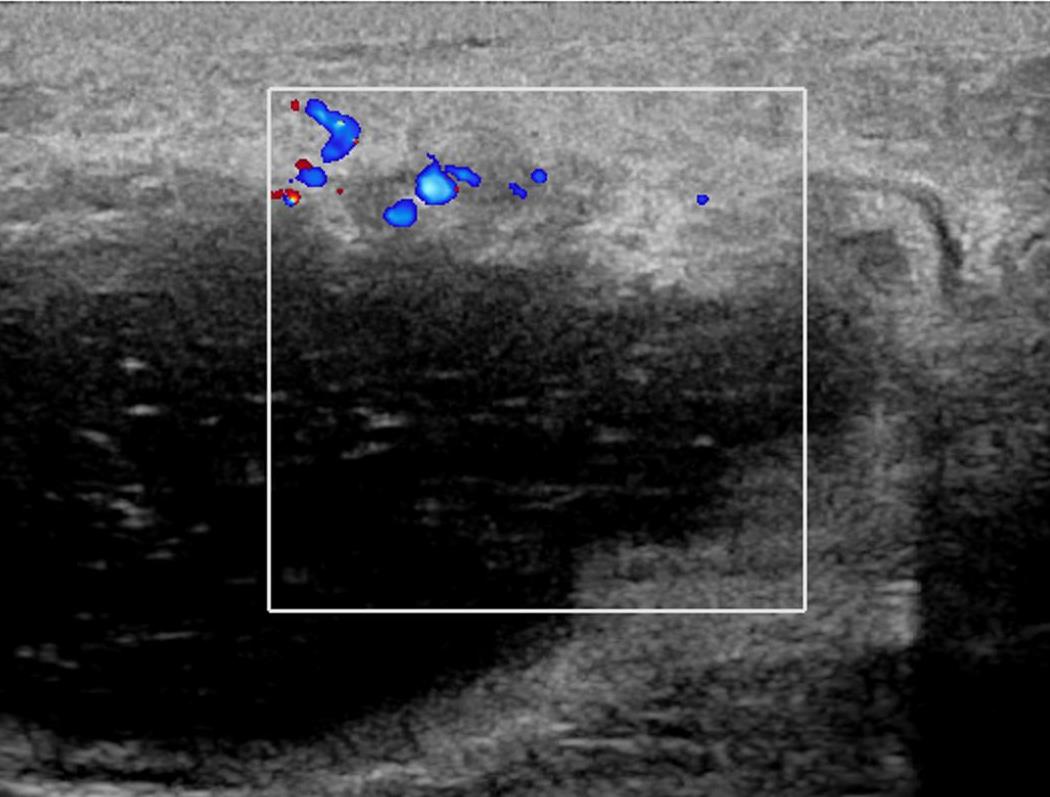

Ultrasound commonly shows irregular hypoechoic confluent mass with tubular extensions, circumscribed hypoechoic mass, skin thickening and edema with axillary lymphadenopathy having reactive features. Less common features include heterogeneous hypoechoic confluent masses with indistinct, lobulated or angular margins, parenchymal distortion with no discrete masses and heterogeneous parenchyma with edema. The lesions and surroundings show increased vascularity. The findings will be normal in 4-20% of the cases. With advanced disease, fluid collections or abscesses may be present.

Ultrasound showed at 12 o’clock position in retroareolar region, a complicated cyst with thick nodular wall measuring 4.4x3.1x5.0 cm. Right axilla showed two round LN with effaced hila measuring 0.6 cm.